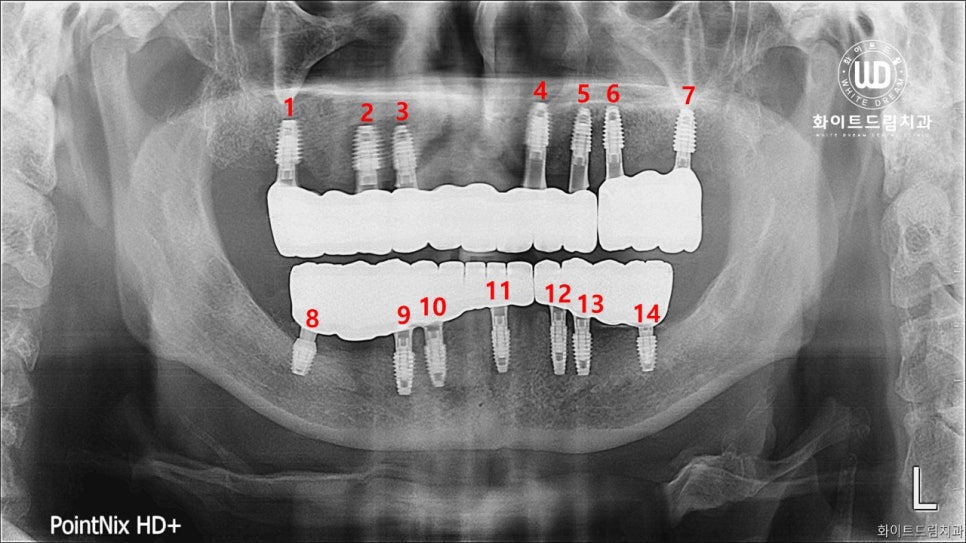

다음은 저작상태를 감안하여 임플란트 나사를 식립한 사진입니다. 임플란트를 한 번에 다수 식립하게 되면 치과 내원 횟수는 줄일 수 있지만, 수술 시간이 길어 피로도가 높아지게 되는데요. 환자분의 건강에 문제가 되지 않도록 고령이신 점에 맞게 진행하여, 하악 임플란트 식립은 통증이 적고 짧은 수술 시간을 위해 반반 나눠서 도와드렸습니다.

상악, 하악 임플란트 보철 제작은 스캐너를 통해 환자분의 구강 정보를 얻고, 컴퓨터를 통해 보철물을 디자인했습니다. 미리 컴퓨터 상에서 보철물을 재현하여 실제 보철제작 전에 적합성을 확인할 수 있도록 도와드렸으며, 치과 내원 횟수를 감소시켜드려 부담이 적어지도록 진행해드렸습니다.

진행한 치료 기간은 약 5개월 정도 소요되었습니다. 고령이신 만큼 치료는 급하지 않게 충분한 시간을 들여 진행하였고, 잇몸전체에 무리가 가지 않도록 보철을 최소식립하였으며, 앞니쪽의 경우 잇몸뼈가 너무 얇아 식립이 어려운점을 고려, 임플란트브릿지를 사용하였습니다.

상악 전체와 하악은 2번, 2주 간격으로 3번에 걸쳐 임플란트 고정체를 식립해 드렸으며, 4개월 동안 임플란트 고정체가 뼈에 잘 유착되도록 기다렸다가 보철 인상채득을 진행하였습니다.